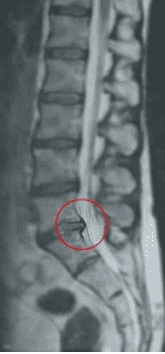

Przykład